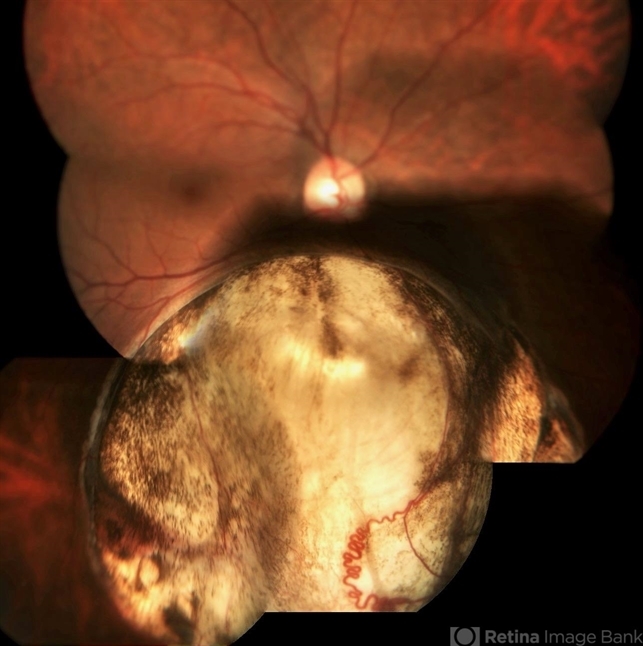

- Fundus photo montage of a 32-year-old female with a retinochoroidal coloboma Ida Mann classification type 3 with a spring coil shaped aberrant vessel.